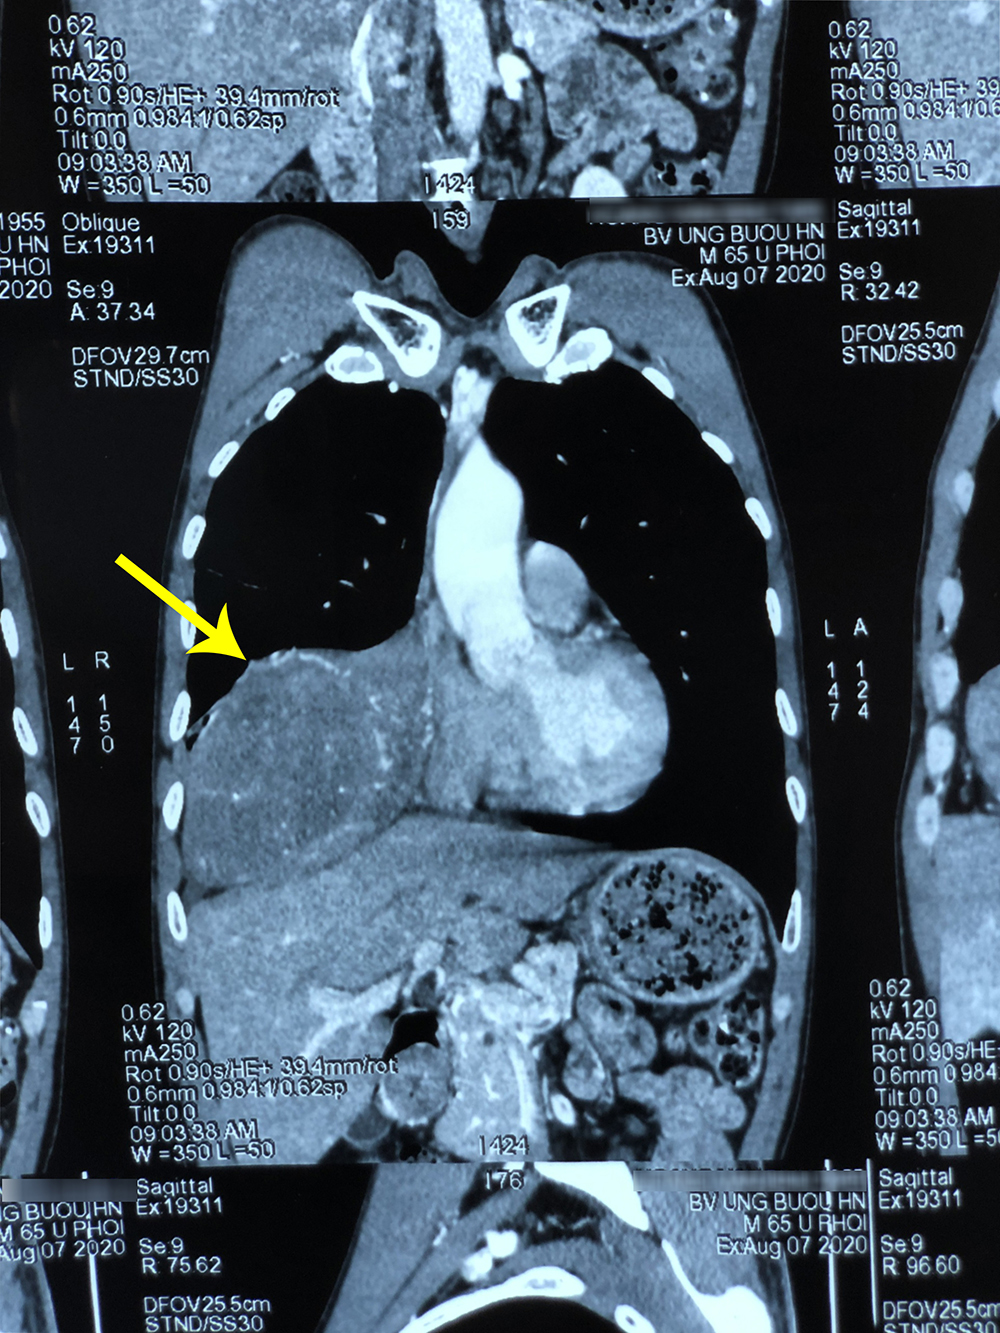

Đó là trường hợp của bệnh nhân H.V.B, 65 tuổi, trú tại Phú Xuyên, Hà Nội. Ông B. cho biết, cách đây khoảng 2 tháng, ông thấy đau nhói bên ngực phải mỗi lần nằm nghiêng và trở mình. Tình trạng đau tức ngày càng tăng gây mệt mỏi nên ông B. quyết định đi khám và được chẩn đoán u phổi phải. Kết quả chụp cộng hưởng từ và cắt lớp vi tính cho thấy phổi phải có khối u kích thước 11x18cm ở vị trí xuất phát tại màng phổi vùng vòm hoành phải đè ép các thùy phổi, xung quanh có tổn thương dạng đông đặc, gây xẹp phổi. Nếu không phẫu thuật sớm, u phát triển lớn sẽ chèn ép gây đau đớn, tức ngực, khó thở và xẹp phổi phải, nếu chèn ép vào trung thất còn có thể ảnh hưởng đến nhịp tim.

Hình ảnh khối u chiếm 2/3 thể tích phổi phải